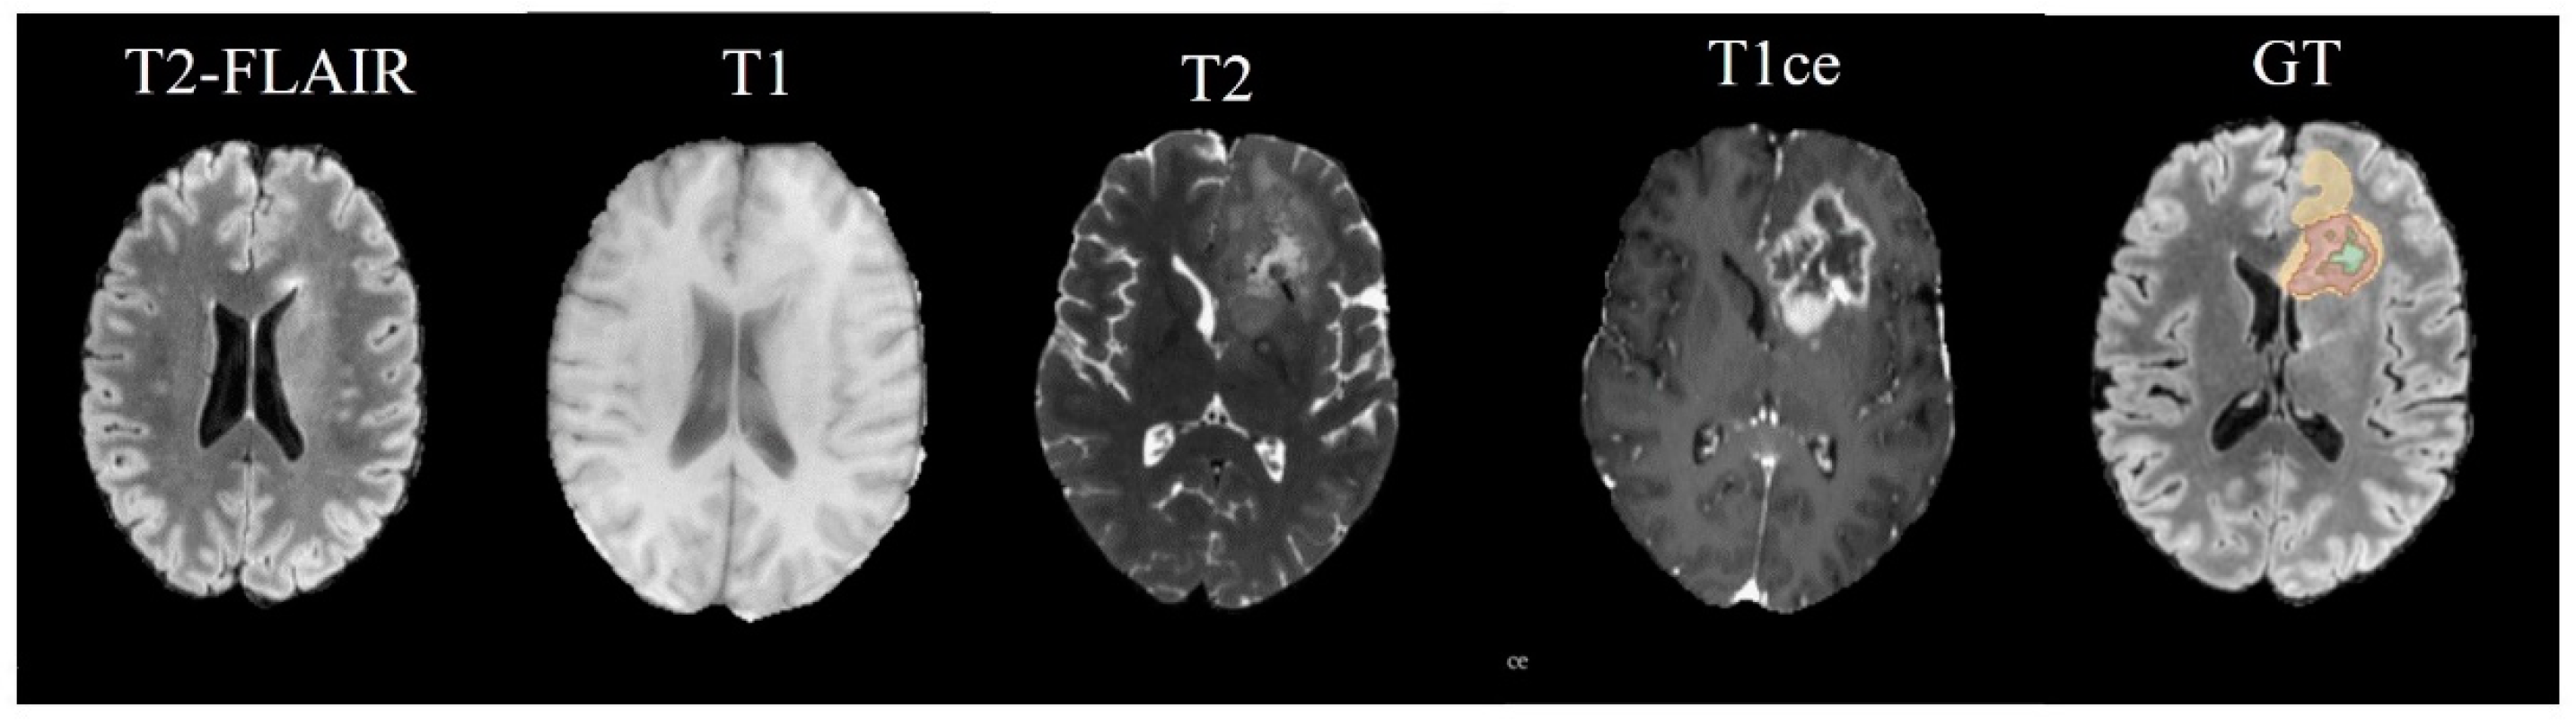

BRATS21 is a large-scale brain multimodal MR Glioma segmentation dataset, including 8160 MRI scans from 2040 patients. Among them, 1251 cases of data were used as training sets and publicly labeled, while 219 cases of data were divided into validation sets and 570 cases of data were used as test sets. MR Images are given for each patient in four modalities in Figure 4.

• Native (T1) scans;

• Post-contrast T1-weighted scans with Gadolinium (T1Gd);

• T2-weighted (T2) scans;

• T2 Fluid Attenuated Inversion Recovery (T2-FLAIR) volumes.

Figure 4. The first four images from left to right show the MRI modalities used as input channels to various Arouse-Net models and the fifth image shows the ground truth labels. The enhanced tumor (ET) from edema/necrotic tissue (ED) is differentiated and the necrotic tumor core (NCR) is delineated within the complexities of medical image segmentation.